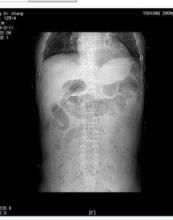

根據病史、症狀體徵、X線檢查可發現膈下游離氣體、腹部超聲、CT等檢查,不難診斷。但診斷過程中一定要明確穿孔部位、穿孔病因來指導治療。